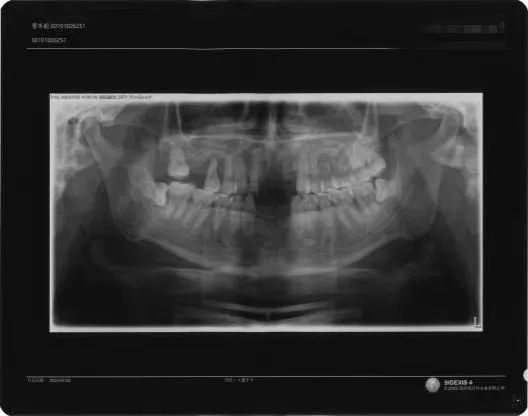

法医临床的司法鉴定人对被鉴定人伤情进行了询问和检查,结合案情、病历记载、影像学片、伤后照片以及被鉴定人既往病史,按照《法医临床检验规范》《法医临床影像学检验实施规范》《人体损伤程度鉴定标准》等标准对被鉴定人管某进行伤情成伤评定、人体损伤程度评定。

被鉴定人在被他人打伤前,就已缺失下方三颗门牙,导致上方三颗门牙对外力的抵抗作用减小,同等外力作用下更易造成严重的损害后果。通过观察被鉴定人伤后脱落牙齿的照片,可见牙根内1/2处光滑,外1/2处存在部分牙石及软组织,存在牙槽嵴萎缩等情况。

综上所述,鉴定机构结合案情、病历记载、影像学片、伤后照片及被鉴定人既往史,考虑被鉴定人上方三颗门牙创伤性牙脱位系本次外伤与被鉴定人既往疾病共同作用所致,依据《人体损伤程度鉴定标准》规定,出具鉴定意见书:被鉴定人管某创伤性牙脱位符合外力直接作用于上唇部所致的损伤;被鉴定人管某的损伤程度构成轻微伤。该鉴定意见被办案机关采纳。